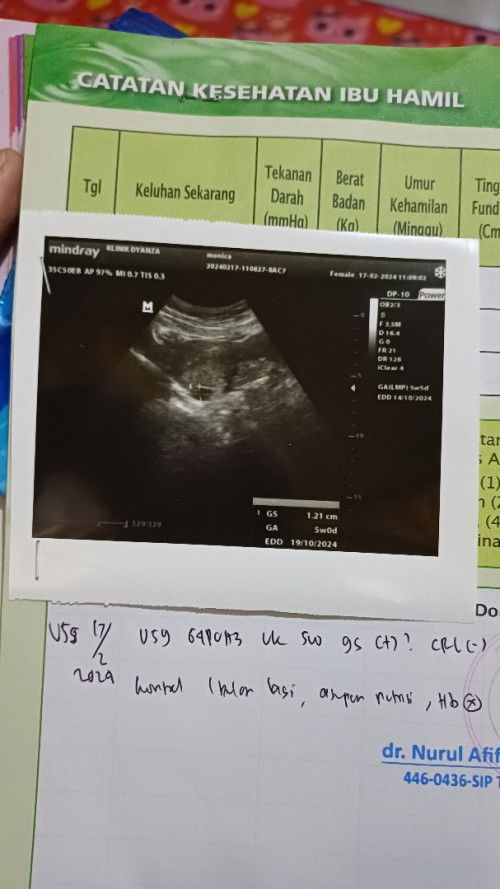

Wajarkah Hamil Usia 5w Kantung Terlihat Kecil?

halo teman², wajar gak ya barusan saya usg usia masih 5w. pas di cek kantungnya cuma lingkaran kecil aja katanya belum kelihatan dan disuruh usg lagi bulan depan. apa wajar bun?